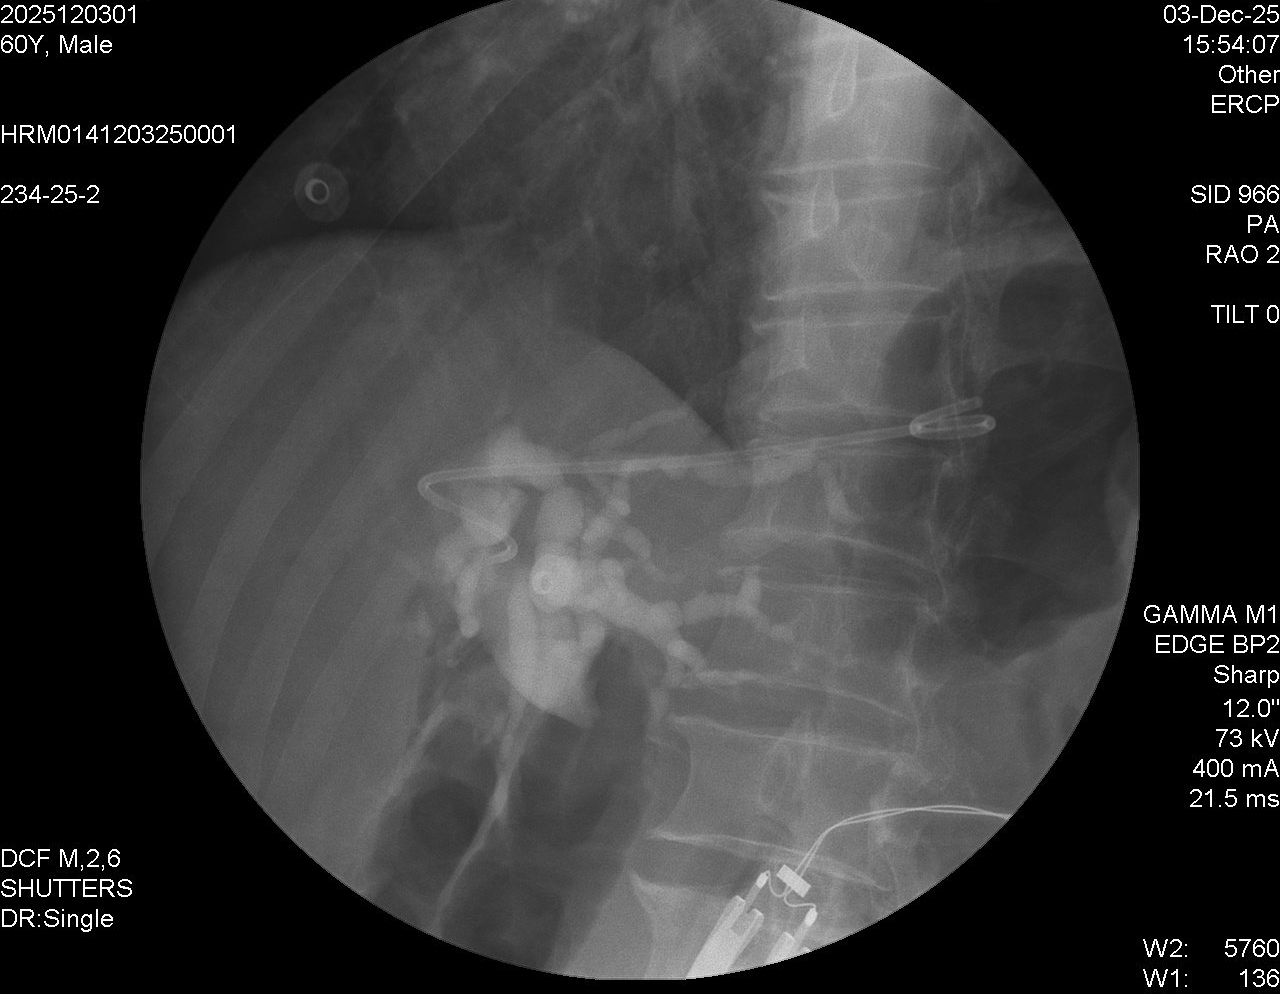

肝內(nèi)膽管與胃之間支架置入后。

經(jīng)過術(shù)前全面評估及精心準備,貴醫(yī)附院消化內(nèi)鏡中心張偉光副主任醫(yī)師在超聲內(nèi)鏡下尋找到能避開血管的最佳穿刺點,將穿刺針刺入肝內(nèi)擴張的膽管,并在X線和超聲內(nèi)鏡雙重輔助下,順利完成導絲置入、切開擴張、支架置入等關(guān)鍵步驟,手術(shù)40分鐘順利完成。